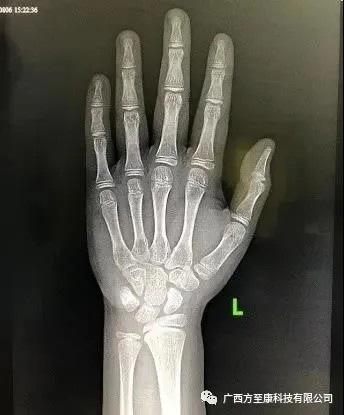

骨龄是骨骼年龄的简称,需要借助于骨骼在X光摄像中的特定图像来确定,通过X线片观察骨化中心的大小、形态、结构和相互关系的变化来判断体格和生理的发育程度。

在未成年人的骨骼X线片中,我们可以发现骨的两端存在着非常特殊的区域——骨骺和生长板,骨骼变长就是通过这一区域的生长来实现的。同时,随着年龄的增长,骨骺的生长逐渐缓慢,生长板逐渐变薄,最终完全与骨骺融合后便不会生长,人也就不能继续长高。

其实拍骨龄非常简单,只需要带孩子去正规医院,通常要拍摄左手手腕部位的X光片,医生通过X光片观察左手掌指骨、腕骨及桡尺骨下端的骨化中心的发育程度,来确定骨龄。